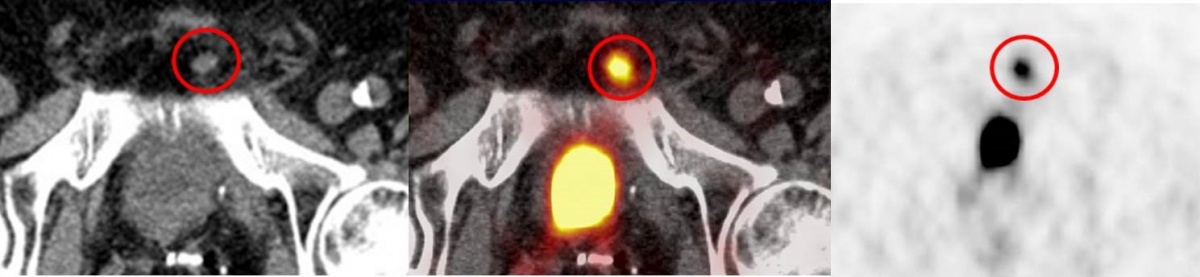

In einem zweiten Fall konnte ein kleiner, 9 x 8 mm messender Lymphknoten links infrapubisch mit deutlich gesteigerter PSMA–Avidität im PET/CT aufgrund des sogenannten „Halo-Artefaktes“ im PET/MRT nicht verifiziert werden. Der Lymphknoten wies einen erhöhten standardized uptake value (SUV) im PET/CT von 10,1 auf und war somit als eindeutig malignomsuspekt zu werten (Abbildung 4). Im MRT kam der Lymphknoten morphologisch als T2-hyperintens zur Darstellung, zeigte jedoch aufgrund eines ausgedehnten Halo-Effektes keine gesteigerte PSMA–Avidität im PET/MRT (Abbildung 5). In der Literatur wird der „Halo-Artefakt“ als typische Artefaktbildung im PET/MRT, die die Detektion von malignen Läsionen nahe der Harnblase bzw. der Nieren beeinträchtigt, beschrieben [3, 21].

MRT (links, Sequenz: STIR transversal) ohne Nachweis einer gesteigerten PSMA-Avidität im PET (rechts)